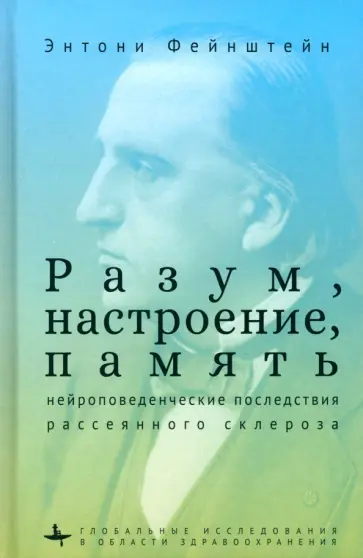

Глобальное бремя болезней: Инфографика и статистика